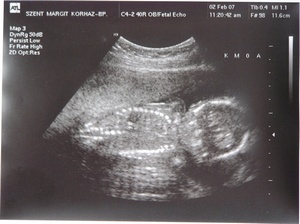

Sziasztok! Na, sikerült lefényképeznem a tegnapi uh képet:

Kép

Dorka: Hol a kukija? Ezen kéne látnom?

Köszönöm a gratokat. Nem, ezen a képen nem látszik a kukaca, de csak ezt az egy képet kaptuk.